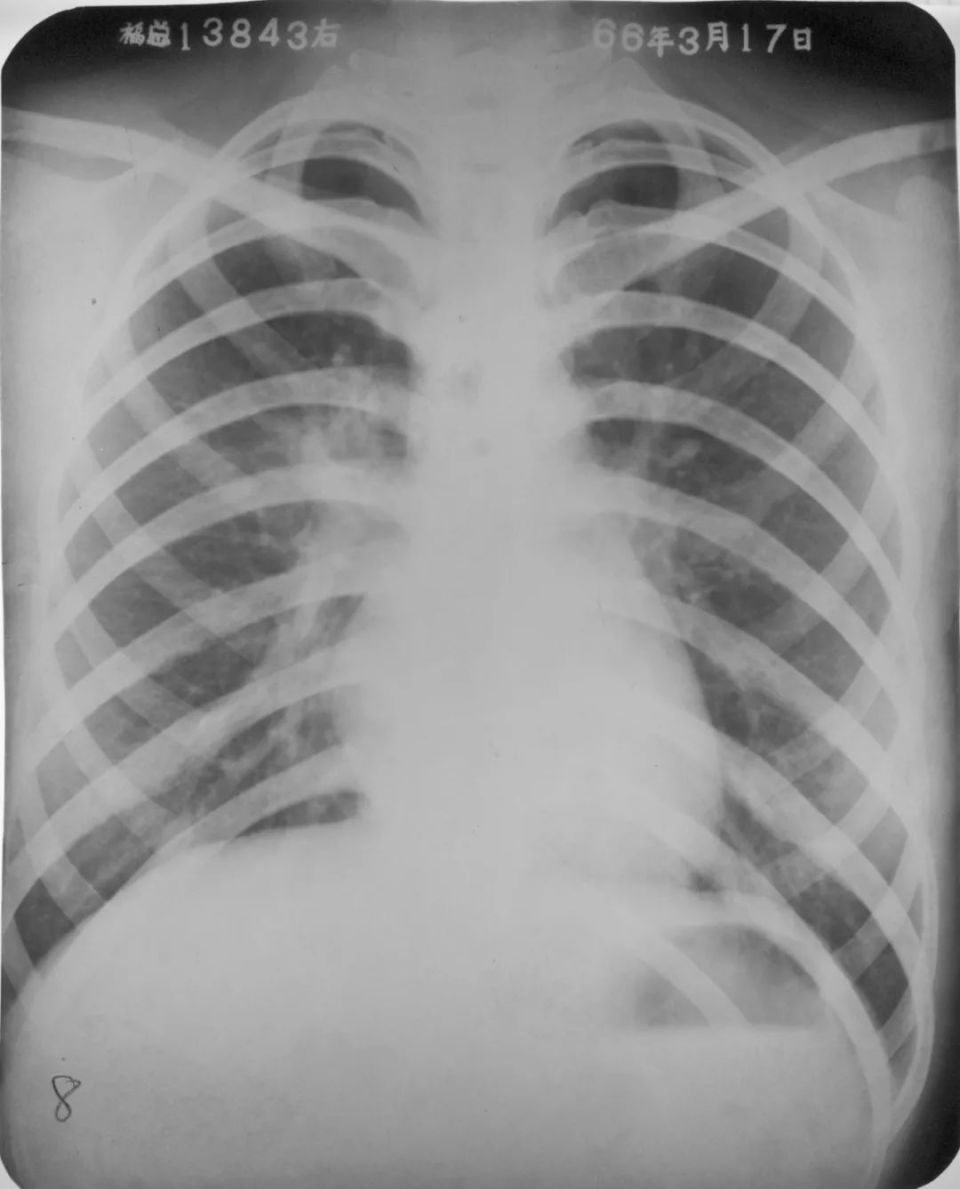

右肺下叶背段大叶性肺炎正侧位

图片

胸部正侧位片:右肺下叶背段见片状、三角形致密影,边缘模糊(箭头所指)